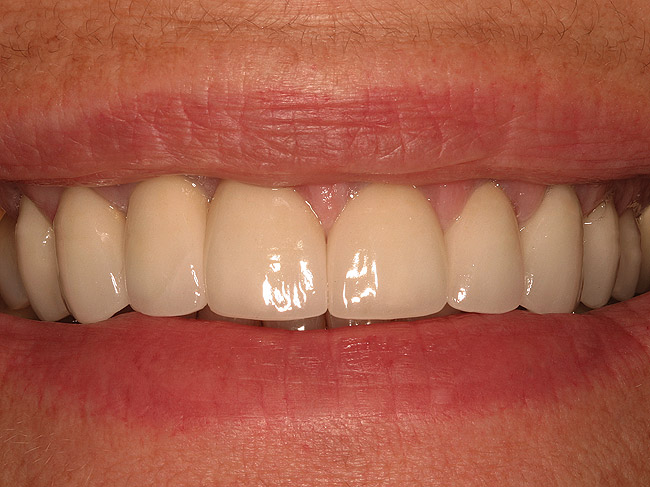

Figure 22  (Case 2) Final smile with anterior restorations in place.

Figure 22